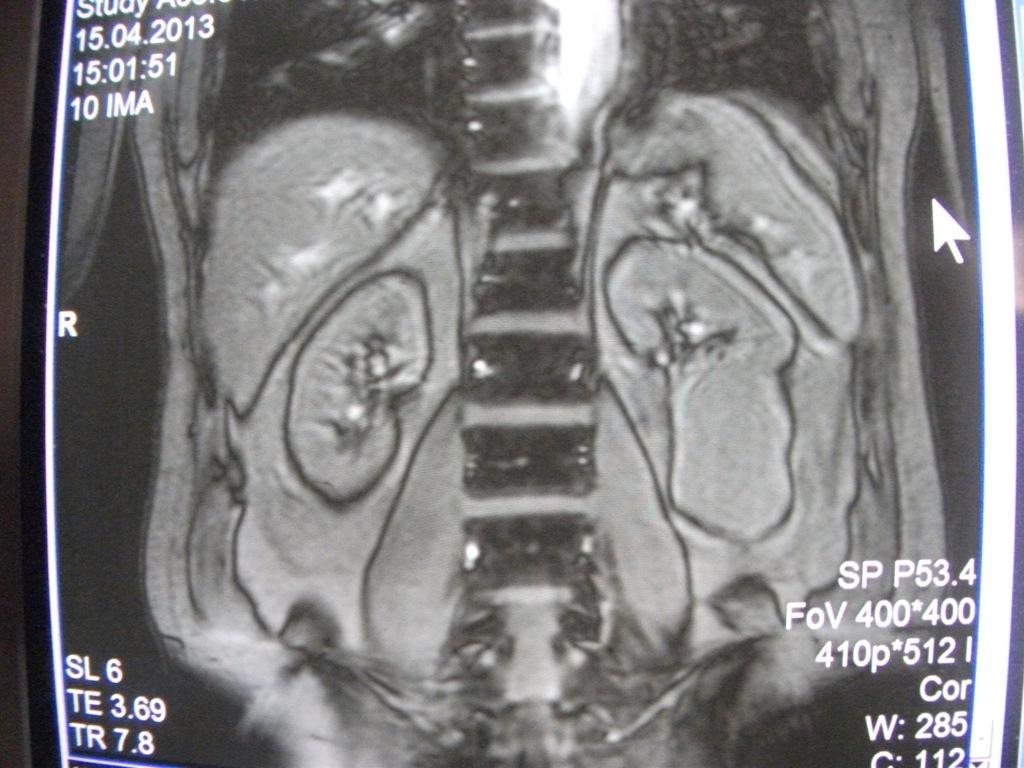

такое заключение: Левая почка: расположена обычно, увеличена, общими размерами около 13х5,5см. В области средней и нижней трети почки определяется объёмное образование неправильной формы, деформирующее наружный контур почки, распространяющиеся с чашечно-лоханочную систему. Опухоль имеет четкие неровные бугристые контуры с наличием псевдокапсулы, неоднородной структуры с признаками распада, максимальными размерами около 78,7х47х48мм